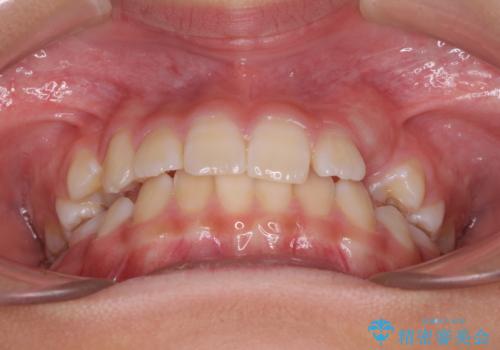

今後残っている乳歯が抜け、永久歯が萌出してくるため、調整可能なリンガルアーチを用いて保定を行っています。

12歳臼歯が萌出するまで経過観察を行い、すべての歯が萌出した後に、全顎矯正治療(Ⅱ期治療)を行っていきます。